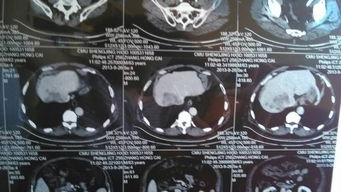

病情分析:您好,您的情況主要是谷丙轉(zhuǎn)氨酶指標(biāo)過(guò)高,這樣的話一般是重點(diǎn)進(jìn)行上腹部的CT掃描,目的是了解肝臟有無(wú)異常病變。